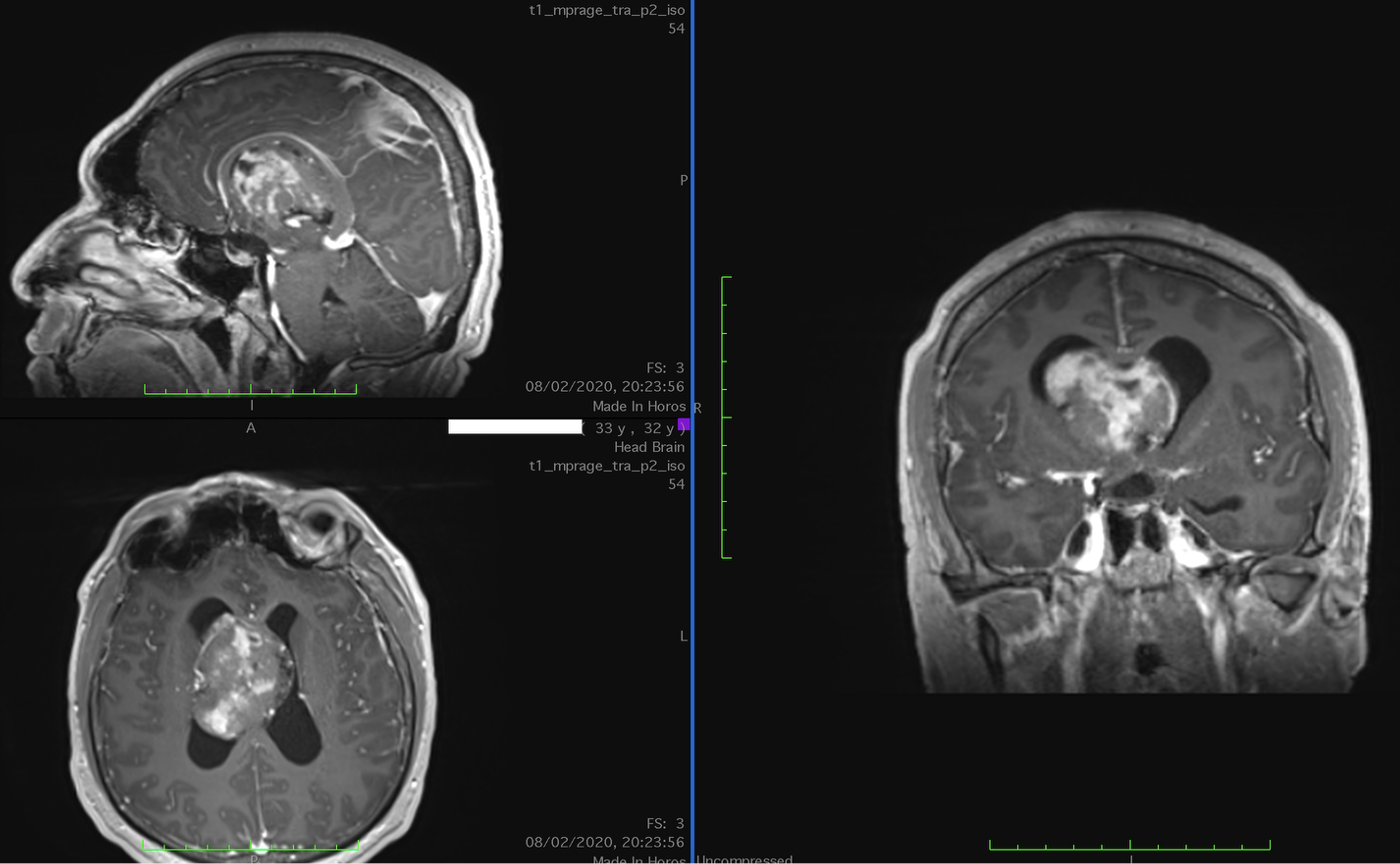

Imaginile arată tumora pre și postop. A fost realizat un abord interemisferic cerebral minim invaziv (keyhole). Rezultatul HP sugerează diagnosticul de neurocitom central, un diagnostic cu prognostic bun.

Femeie, în vârstă de 32 de ani

Simptome - dureri de cap nou apărute, cu creștere în intensitate

Diagnostic HP Neurocitom central Grad OMS: II

Intervenție - Abord interemisferic keyhole

Status actual - Fără recidivă la 5 ani Externată fără deficit neurologic